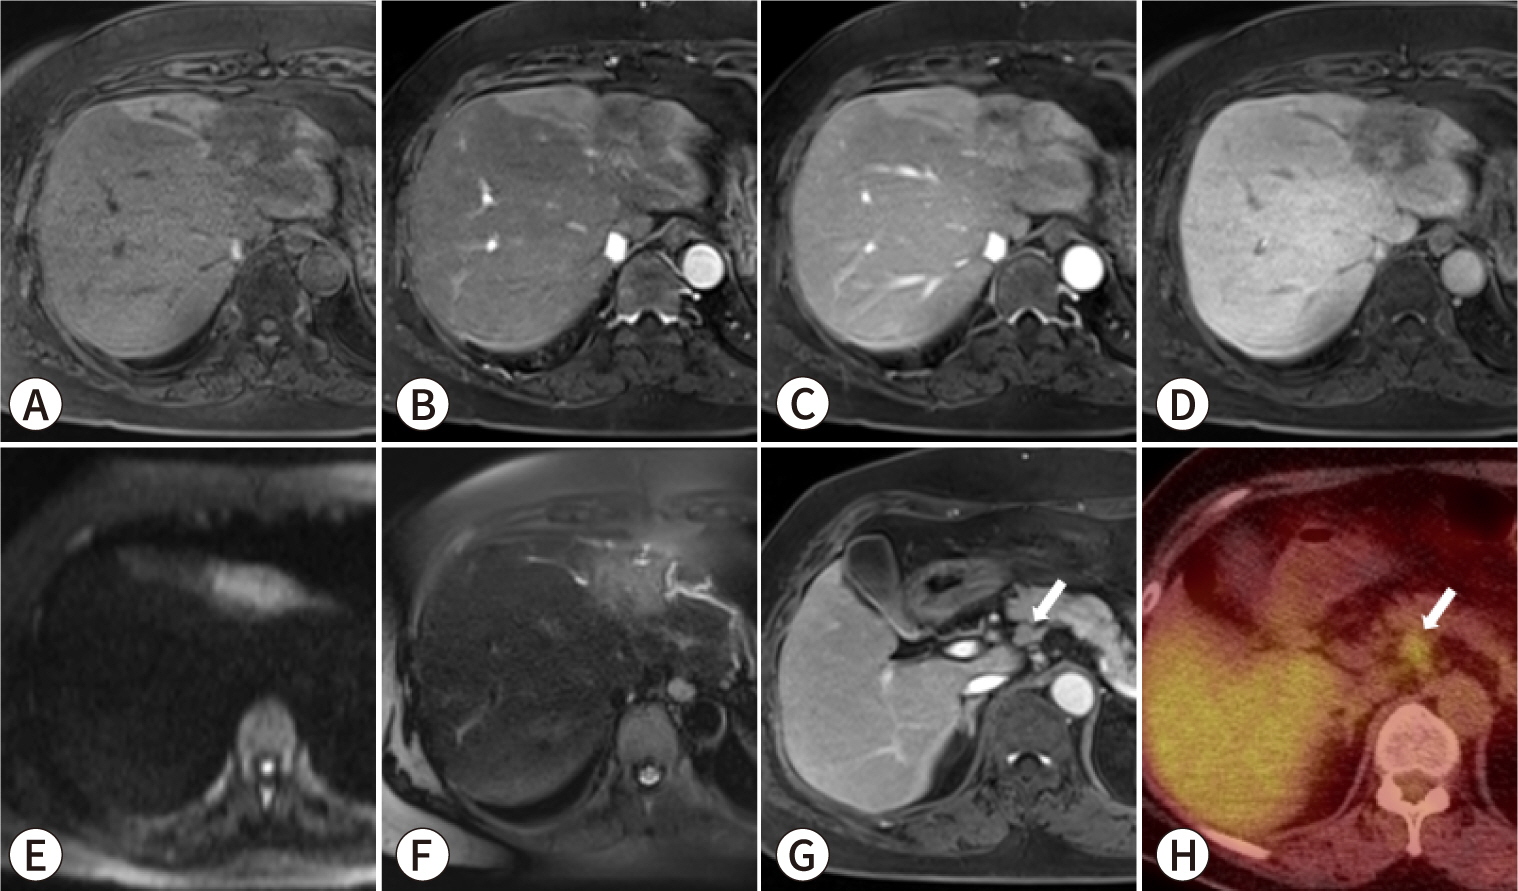

Fig. 5.

A 64-year-old female patient with intrahepatic cholangiocarcinoma (iCCA) and lymph node metastasis. Gadoxetic acid-enhanced MRI, comprising (A) pre-contrast T1-weighted, (B) arterial phase, (C) portal phase, (D) hepatobiliary phase, (E) diffusion-weighted (b=800 s/mm2), and (F) T2-weighted images, reveals a 3.5-cm infiltrative, poorly enhancing mass in the left lobe, with adjacent bile duct dilatation. Additionally, the (G) portal phase image and (H) 18F-fluorodeoxyglucose (18F-FDG) positron emission tomography-CT display an enlarged lymph node with increased 18F-FDG uptake situated adjacent to the common hepatic artery (white arrows). The patient underwent left hepatic lobectomy with lymph node dissection, and pathological examination confirmed the diagnosis of iCCA with regional lymph node metastases.